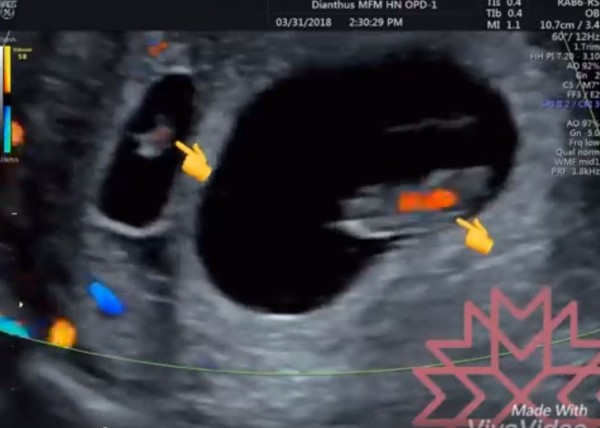

妊娠4週目のエコー写真 胎芽や胎嚢 初期症状や流産のこと 妊娠初期 All About

妊娠5週目 胎嚢の大きさ エコー写真 つわり症状や流産のこと 妊娠初期 All About